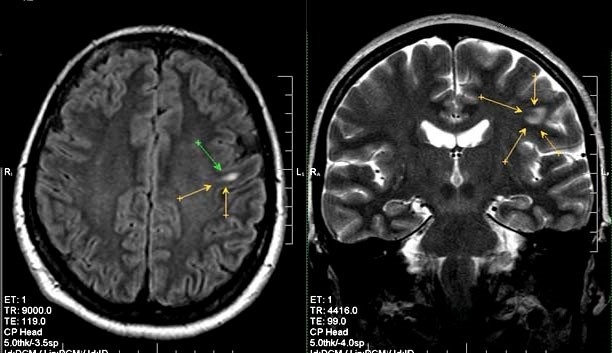

Для постановки диагноза применяют методики нейровизуализации: МРТ И КТ головного мозга. Оба метода позволяют определить локализацию, размеры, количество очагов кистозно-глиозной трансформации. Однако МРТ позволяет точно определить наличие мелких образований. Использование КТ с контрастом необходимо для диагностики отклонений, которые имеют сосудистый генез.

Важно! МРТ позволяет диагностировать глиоз белого вещества, расположенного в лобных долях. Болезнь невозможно определить при помощи иных методик.